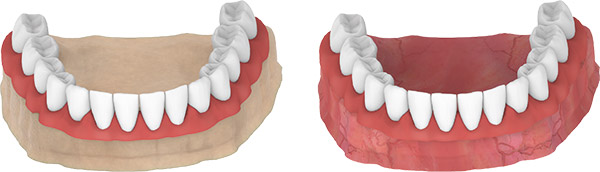

DENT LAB PROCESS

- Carefully mount the open-tray impression post to analogs.

- Apply slight manual torque (5-10 Ncm).

- Apply silicone around the analogs to prepare the removable gingival mask.

- Cast high quality plaster for the master model.

- The sleeves are used in the laboratory for modeling.

- The model is restored in the dental laboratory.

- Place all prosthetic bridge connections on the abutment.

- Tighten the prosthetic screws with 15 Ncm using the torque ratchet and driver.

- Cover the screw holes in the prosthesis with protective material and apply composite.

- Check the occlusion.